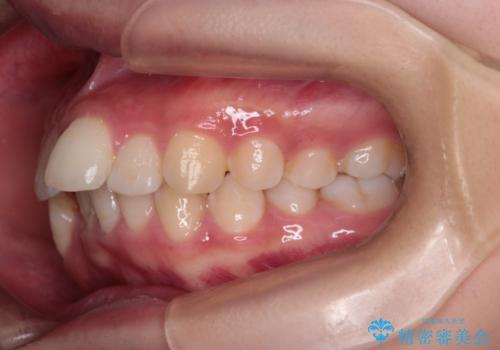

重度の歯のがたつきを、目立たない矯正と抜歯で根本改善

- 前歯から奥歯にかけて歯の重なりが激しい歯のがたつき(重度叢生)を主訴にご来院されました。精密検査の結果、歯が並ぶスペースが大幅に不足しており、歯並びを整え、口元を美しく引っ込めるためには、スペースの確保が必要と診断しました。そこで、上下左右の第一小臼歯(4番目の歯)を計4本抜歯し、そのスペースを利用して歯並び全体を整える抜歯矯正の治療計画を立案。装置には、透明で目立たないインビザラインを採用し、審美性と治療効果の両立を目指しました。

今回の治療では、重度の叢生を改善するため、まず計画通り上下左右4本の小臼歯を抜歯し、歯を並べるための十分なスペースを確保しました。装置には透明で取り外し可能なインビザラインを使用。抜歯によってできたスペースを最大限に活用し、マウスピースを定期的に交換しながら、デコボコを解消しつつ、前歯を効果的に後退させました。

治療の結果、長年の悩みであった重度の歯のがたつきが解消され、口元の突出感も改善。機能的にも安定し、審美的にも美しい、理想的な歯並びを獲得していただけました。